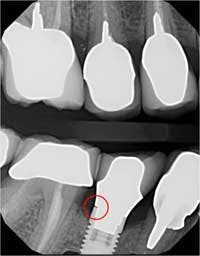

The screw channel of the abutment was accessed by carefully drilling a hole in the center of the occlusal surface using a cross-cut 557 bur (Brasseler) and progressively widening it until the screw channel was accessed (figure 10). Once the screw channel was accessed, the cavit and cotton blocking the screw were removed and the screw was visualized. A driver was placed into the channel to engage the screw and the cement-retained crown was seated on the implant and “screwed” back in place. Complete seating of the restoration was verified radiographically (figure 11). The screw was torqued to 25 Ncm and the access channel was filled with Teflon tape and closed with composite (figure 12). The patient was able to leave with the crown securely in place.

Figure 11:Complete seating of the restoration confirmed radiographically.